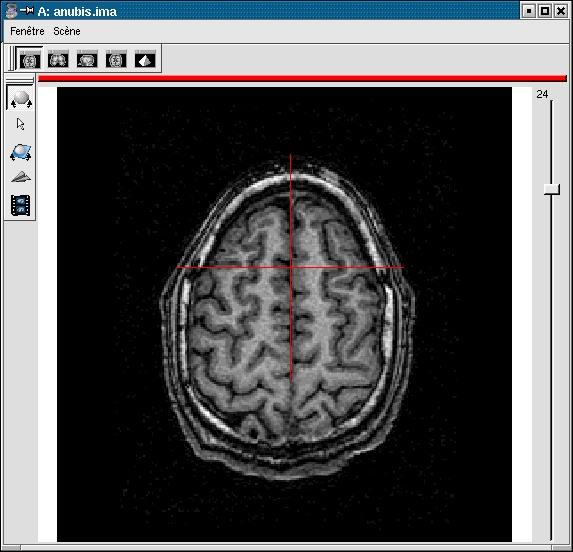

You have to select 3 points (you can use a sagittal slice if you prefer):

- Any point of the interhemispheric plane not aligned with the previous ones.

Inter-hemispheric plane: